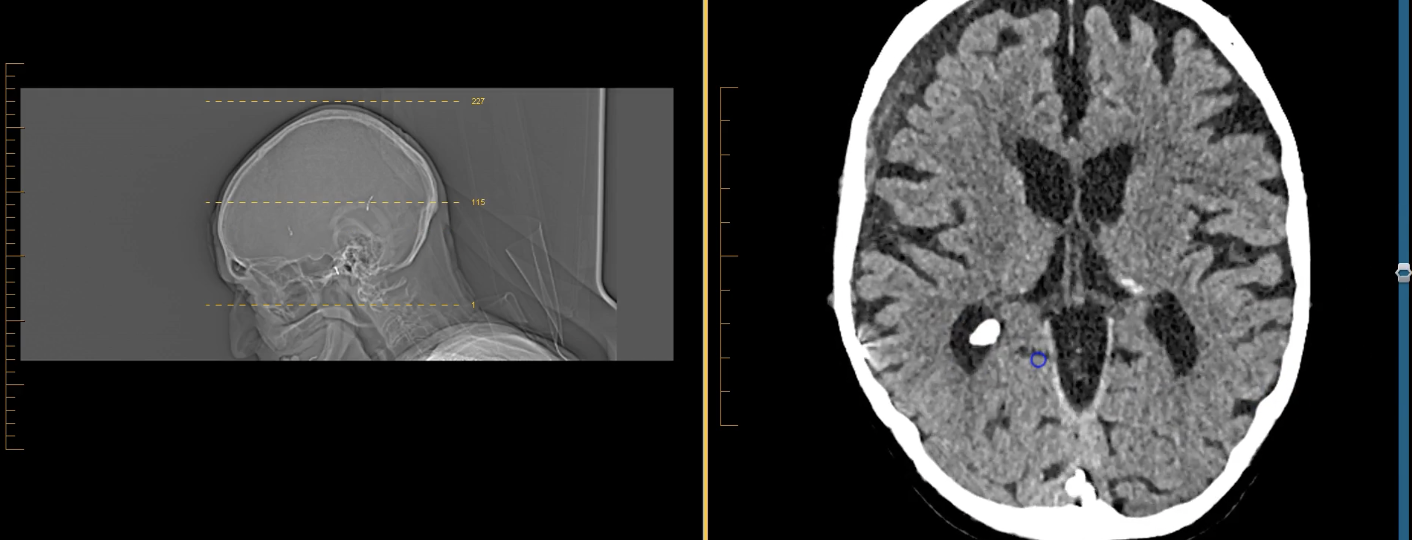

New cards

term image

third ventricles